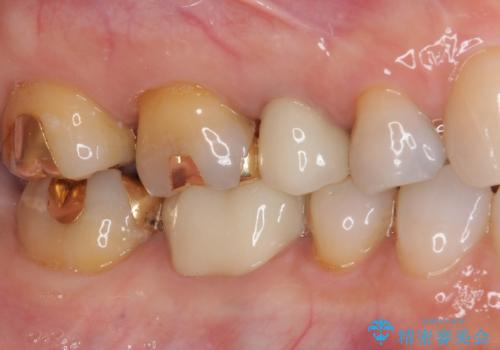

仮歯に変える際に歯肉の一部を切除し、金属片による変色を除去した後、オールセラミッククラウンにて補綴することとしました。

メタルタトゥー(金属イオンの溶出による歯肉の変色)は、歯に装着された金属から金属イオンが溶け出したり、金属を除去するときの切削片が歯肉に入り込んでしまったりして引き起こされます。

物理的に除去をすることできれいな歯肉となりますが、残留している金属イオンにより再発するリスクがあります。